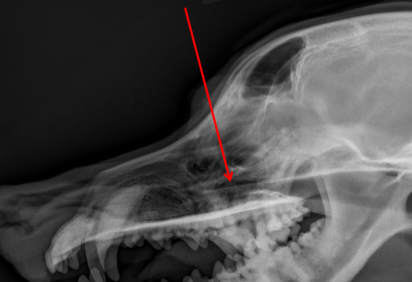

Mandible

ID.

Maxilla

ID

Coronoid Process of Mandible